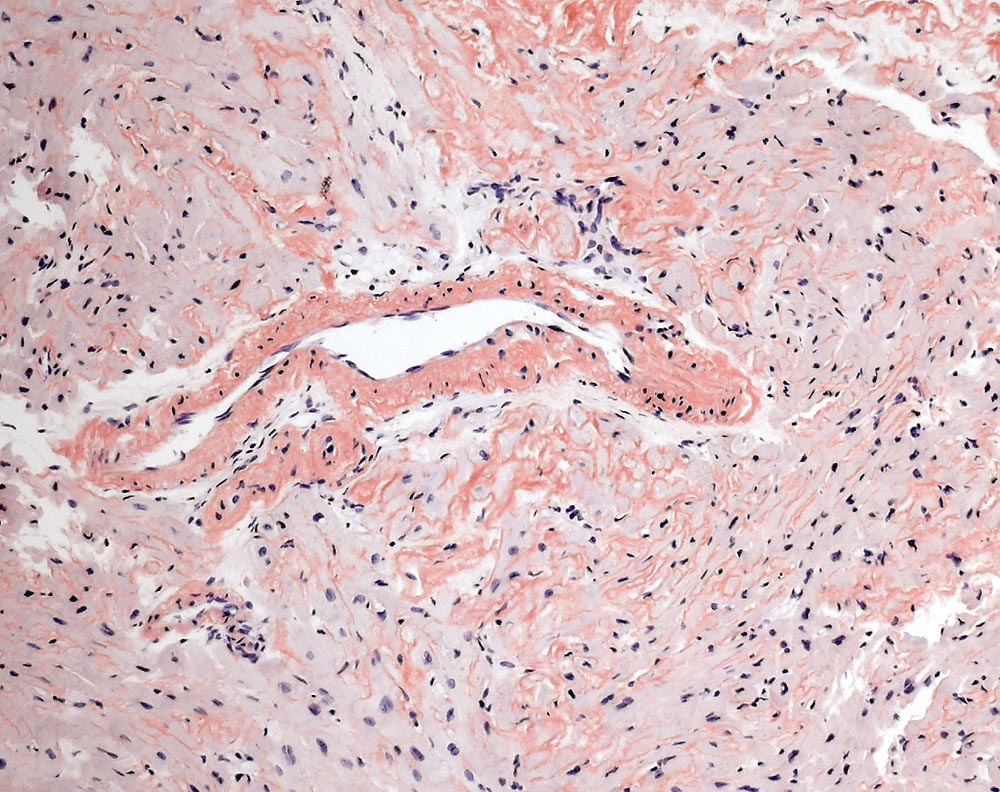

Kardiale AL-Amyloidose

Interstitielle und vaskuläre kongorote Amyloidablagerungen.

Interstitielle Knochenmarksinfiltration durch ein lambdaklonale Plasmazellneoplasie, Infiltrationsvolumen 15-20% der kernhaltigen Knochenmarkszellen. AL-Amyloidose der Knochenmarksgefässe.

Zunehmende Dyspnoe über die vergangenen 2 Jahre. Multiples Myelom mit freien Leichtketten vom Typ Lambda. TTE: Ausgeprägt konzentrisch hypertropher linker Ventrikel mit normaler systolischer Globalfunktion ohne regionale Motilitätsstörungen (EF 60%). Diastolische Dysfunktion Grad 3 bis 4 (restriktive Füllungsmuster).

100